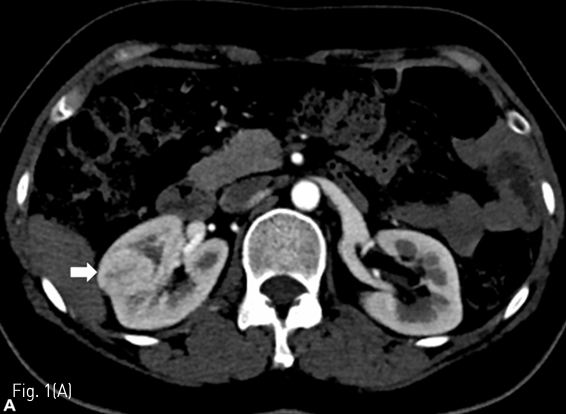

Fig 1A

(A) A 46-year-old female underwent partial nephrectomy for hypervascular mass (arrow) in right kidney.

조영 증강 복부 전산화 단층촬영에서 우측 신장에 renal cell carcinoma로 생각되는 약 3cm 크기의 hypervascular tumor가 있다 (Fig. 1A) 우측 신장 부분 절제술을 시행 받고 5일째 복통을 호소하여 시행한 복부 전산화 단층촬영에서 수술 부위 주변으로 large urinoma with contrast leakage를 확인할 수 있다 (Fig. 1B).